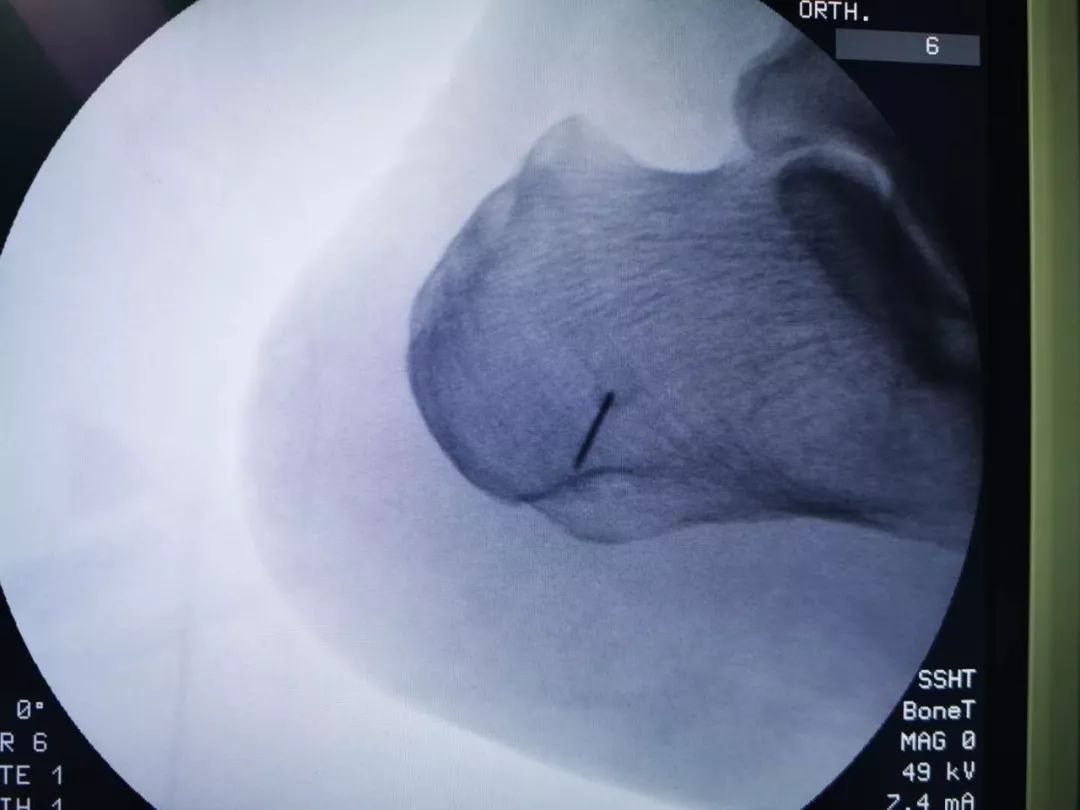

患者骆某 82岁,“反复左足跟疼痛走路困难4年”入院,经X线检查诊断为“左侧跟骨骨刺”。此前患者曾尝试各种治疗方法效果均不理想。

术前检查

骨伤二科主任医师方磊经过与治疗团队认真讨论后,为患者制定了全新的微创手术方案,行关节镜下跟骨骨刺摘除术,手术取足跟部内侧两个0.5cm长小切口,在关节镜监视下切除增生骨赘,清理修整骨刺周围炎性组织,同时行跖筋膜松解,成功完成手术,目前患者术后恢复良好。